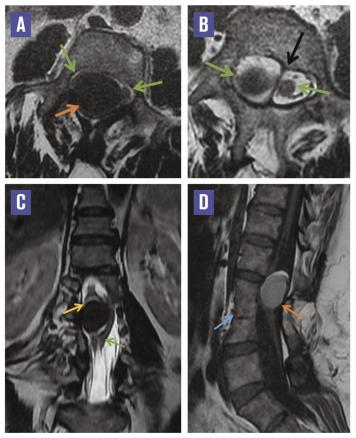

L’imagerie par résonance magnétique mettait en évidence une moelle bas attachée, avec deux hémimoelles lombaires séparées par un éperon fibreux, en regard de L1, associée à un bloc vertébral L2-L3-L4 et à une formation intradurale extramédullaire à la hauteur de L2-L3, refoulant l’hémimoelle droite, bien limitée, en hypersignal T1, hyposignal T2 franc, sans rehaussement après injection de gadolinium. L’ensemble évoquait une diastématomyélie de type II associée à un kyste neurentérique à contenu protéique ou hématique (figure ).

La diastématomyélie est un dysraphisme spinal fermé rare, caractérisé par une division de la moelle épinière en deux cordons, qui s’accompagne souvent d’un éperon osseux ou cartilagineux scindant la moelle.1 Souvent lombaire, elle prédomine chez la femme et se révèle habituellement chez de jeunes patients, rarement à l’âge adulte. Les circonstances de découverte sont variables : douleurs, troubles sensitivomoteurs ou de la sphère génito-urinaire (urgences mictionnelles, incontinence).1 L’imagerie par résonance magnétique (IRM) est l’examen de référence pour étudier le rachis malformatif et analyser le cordon médullaire.

Les kystes neurentériques se développent quant à eux à partir de reliquats de l’endoderme en position ectopique dans le canal rachidien. Ils sont intraduraux, extramédullaires, et se situent au niveau de la jonction cervicothoracique ou du cône terminal. En IRM, ils se présentent comme des structures arrondies de la moelle antérieure, de même signal que le LCR, ou iso-intenses à la moelle en cas de contenu protéique, sans rehaussement après injection de gadolinium. Ces lésions peuvent s’associer à des anomalies vertébrales de type spina-bifida, fusion intervertébrale, diastématomyélie ou à un simple élargissement du canal rachidien.2